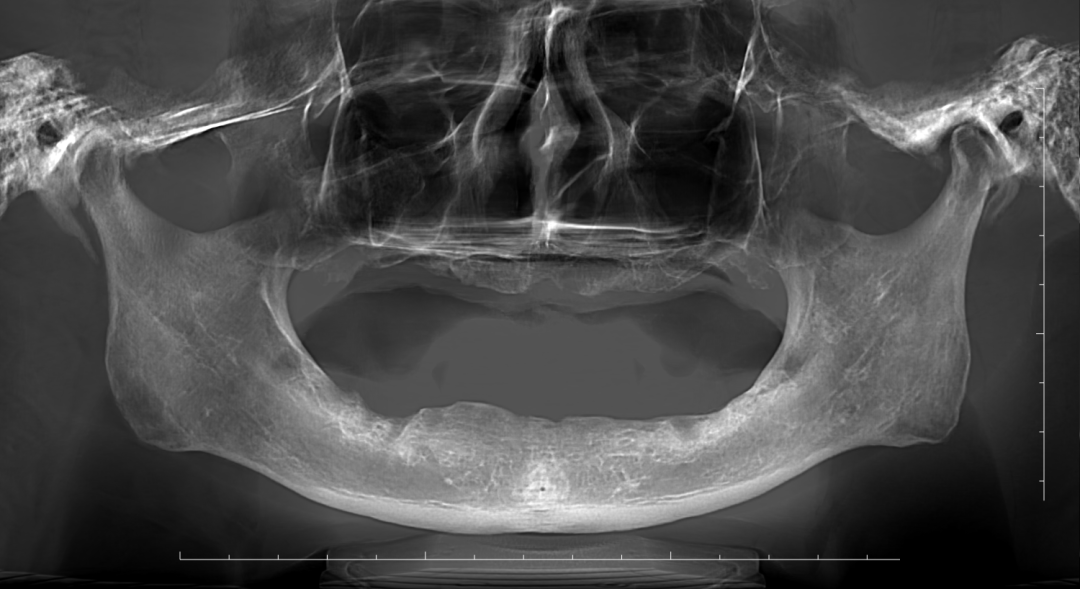

CBCT、口扫数据显示,由于长期缺牙,阮先生上颌牙槽骨几乎消失殆尽,后牙区右侧骨板几乎没有牙槽嵴,传统种植难以实施。车超院长对阮先生颌面部条件、口腔情况、身体条件进行全面的检查评估后,决定通过ZAGA理念、颧种植、鼻甲嵴种植植入4颗种植体,为阮先生实现即刻负重种植。